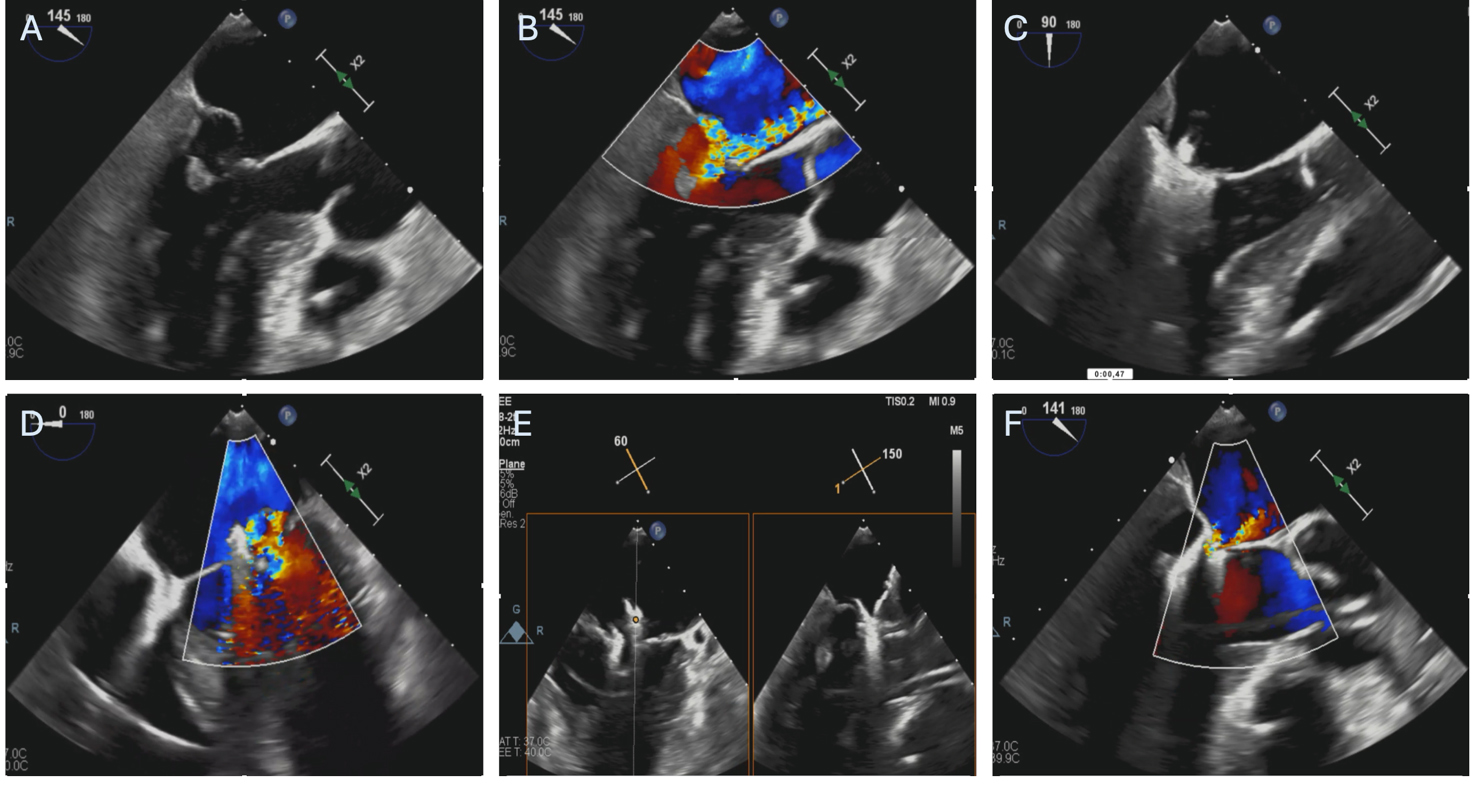

Current evidence for the treatment of ischemic AMR is still limited, but much of it comes from the use of the Mitraclip system. An example of M-TEER performed in a patient with AMR caused by PMR after AMI is represented in Fig. 3.

Fig. 3. Patient with severe mitral regurgitation after myocardial infarction treated with M-TEER. (A,B) Severe mitral regurgitation due to anterolateral papillary muscle rupture and subsequent P2 leaflet flail. (C) First Mitraclip XTW positioning, before grasping. (D) Result after releasing the first Mitraclip XTW. (E) Orientation of the second Mitraclip XTW. (F) Final result after releasing the second. M-TEER, mitral transcatheter edge-to-edge repair.